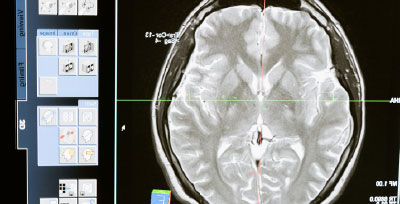

Cerebros más antiguos tienden a padecer enfermedades crónicas

Un estudio presentado en la Conferencia de la Organización Europea del Ictus (ESOC 2022) y dirigido por el doctor Martin Bretzner, de la Facultad de Medicina de Harvard (Estados Unidos) observó que los pacientes con cerebros con características de una edad cerebral prevista superior a la edad cronológica, son más propensos a padecer hipertensión, diabetes mellitus o tener antecedentes de tabaquismo o de accidentes cerebrovasculares previos.